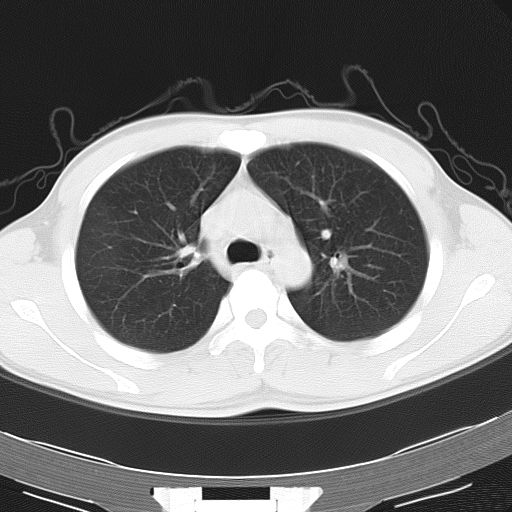

男,34岁,咳嗽2~3个月,无咳血,病初有发热。

病变分布以双上肺叶外带明显,双下肺未见异常,此一点不十分支持肺泡蛋白质沉着症,病变未见铺碎路石征,也不肺泡蛋白质沉着症。考虑间质性肺炎,结核不除外。

肺泡蛋白沉积症;胸膜下区磨玻璃样,实变区见纹理走形,地图样改变。做mri。

ct表现 (1)中央型:表现为蝶翼状浸润性阴影对称分布于两侧肺门周围,其内可见支气管充气征,病变区与正常肺组织分界清楚。(2)外围型:表现为多发性条片状、斑片状及斑块状高密度影,弥散、对称或不对称分布于两肺或一侧肺外围部位。病变区与正常肺组织及脏层胸膜面分界清晰,呈地图样改变。hrct可显示小叶间隔增厚及肺小叶内淡淡的密度增高影等细微结构,同时易发现肺大疱、肺气囊及节段性肺不张。

再仔细阅读该病人的ct片,我们不难发现,病例所表现的正是外围型的肺泡蛋白沉积症表现,即:为多发性条片状、斑片状及斑块状高密度影,弥散、对称或不对称分布于两肺或一侧肺外围部位。病变区与正常肺组织及脏层胸膜面分界清晰,呈地图样改变。